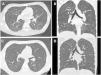

We describe the case of a male adolescent aged 17 years admitted for severe acute respiratory failure with hypoxaemia. During the hospital stay, numerous diagnostic tests were performed, and the findings of the computed tomography scan of the lungs proved key to the diagnosis, with visualization ground glass micronodules with tree-in-bud opacities and a diffuse distribution1 (Fig. 1).

Computed tomography images obtained during the hospital stay. Axial (A and B) and coronal (C and D) images showed small micronodular opacities in a diffuse tree-in-bud pattern, without involvement of the subpleural region. Images B and D evince the presence of consolidations in the right lower lobe.